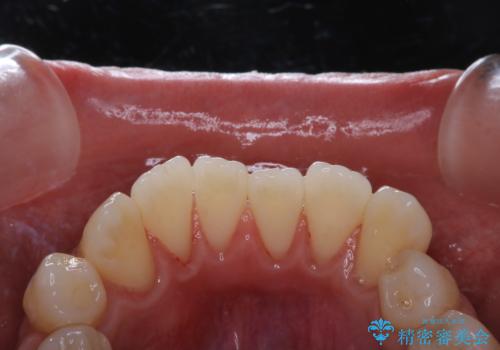

- 歯周病が心配で予防をしていきたいとのことでした。PMTC60分コースを行いました。

歯周病とは、細菌による感染症です。歯周病菌を取り除くには、歯周ポケットの中を機械的に掃除することです。

歯周病の原因は、歯にべったりと付着するプラーク(細菌の塊)や歯石です。そこから歯周病菌が引き起こす炎症により、歯を支える歯周組織が破壊され、最終的には歯が抜け落ちてしまうという怖い病気です。

もっとも、効果的な治療法がPMTC(歯科医院で専門的な機械や材料を使用してクリーニング)を定期的に行うことです。